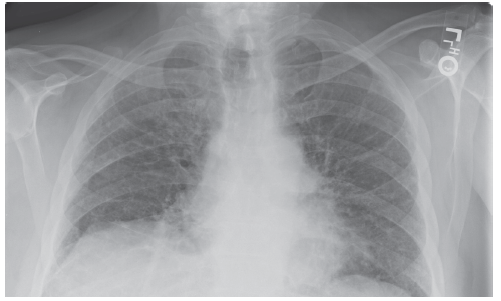

Samuel Louie, MD; Chinh T. Phan, DO

Interstitial lung disease has a history of baffling clinicians for several reasons—2 of those being confusing terminology and classification, which continue to thwart clinicians’ ability to establish a...

Trent Wang, DO; Ronald N. Rubin, MD

Lung cancer screening with low-dose helical CT scanning should be conducted in high-risk individuals after an informed discussion of benefits and risks.